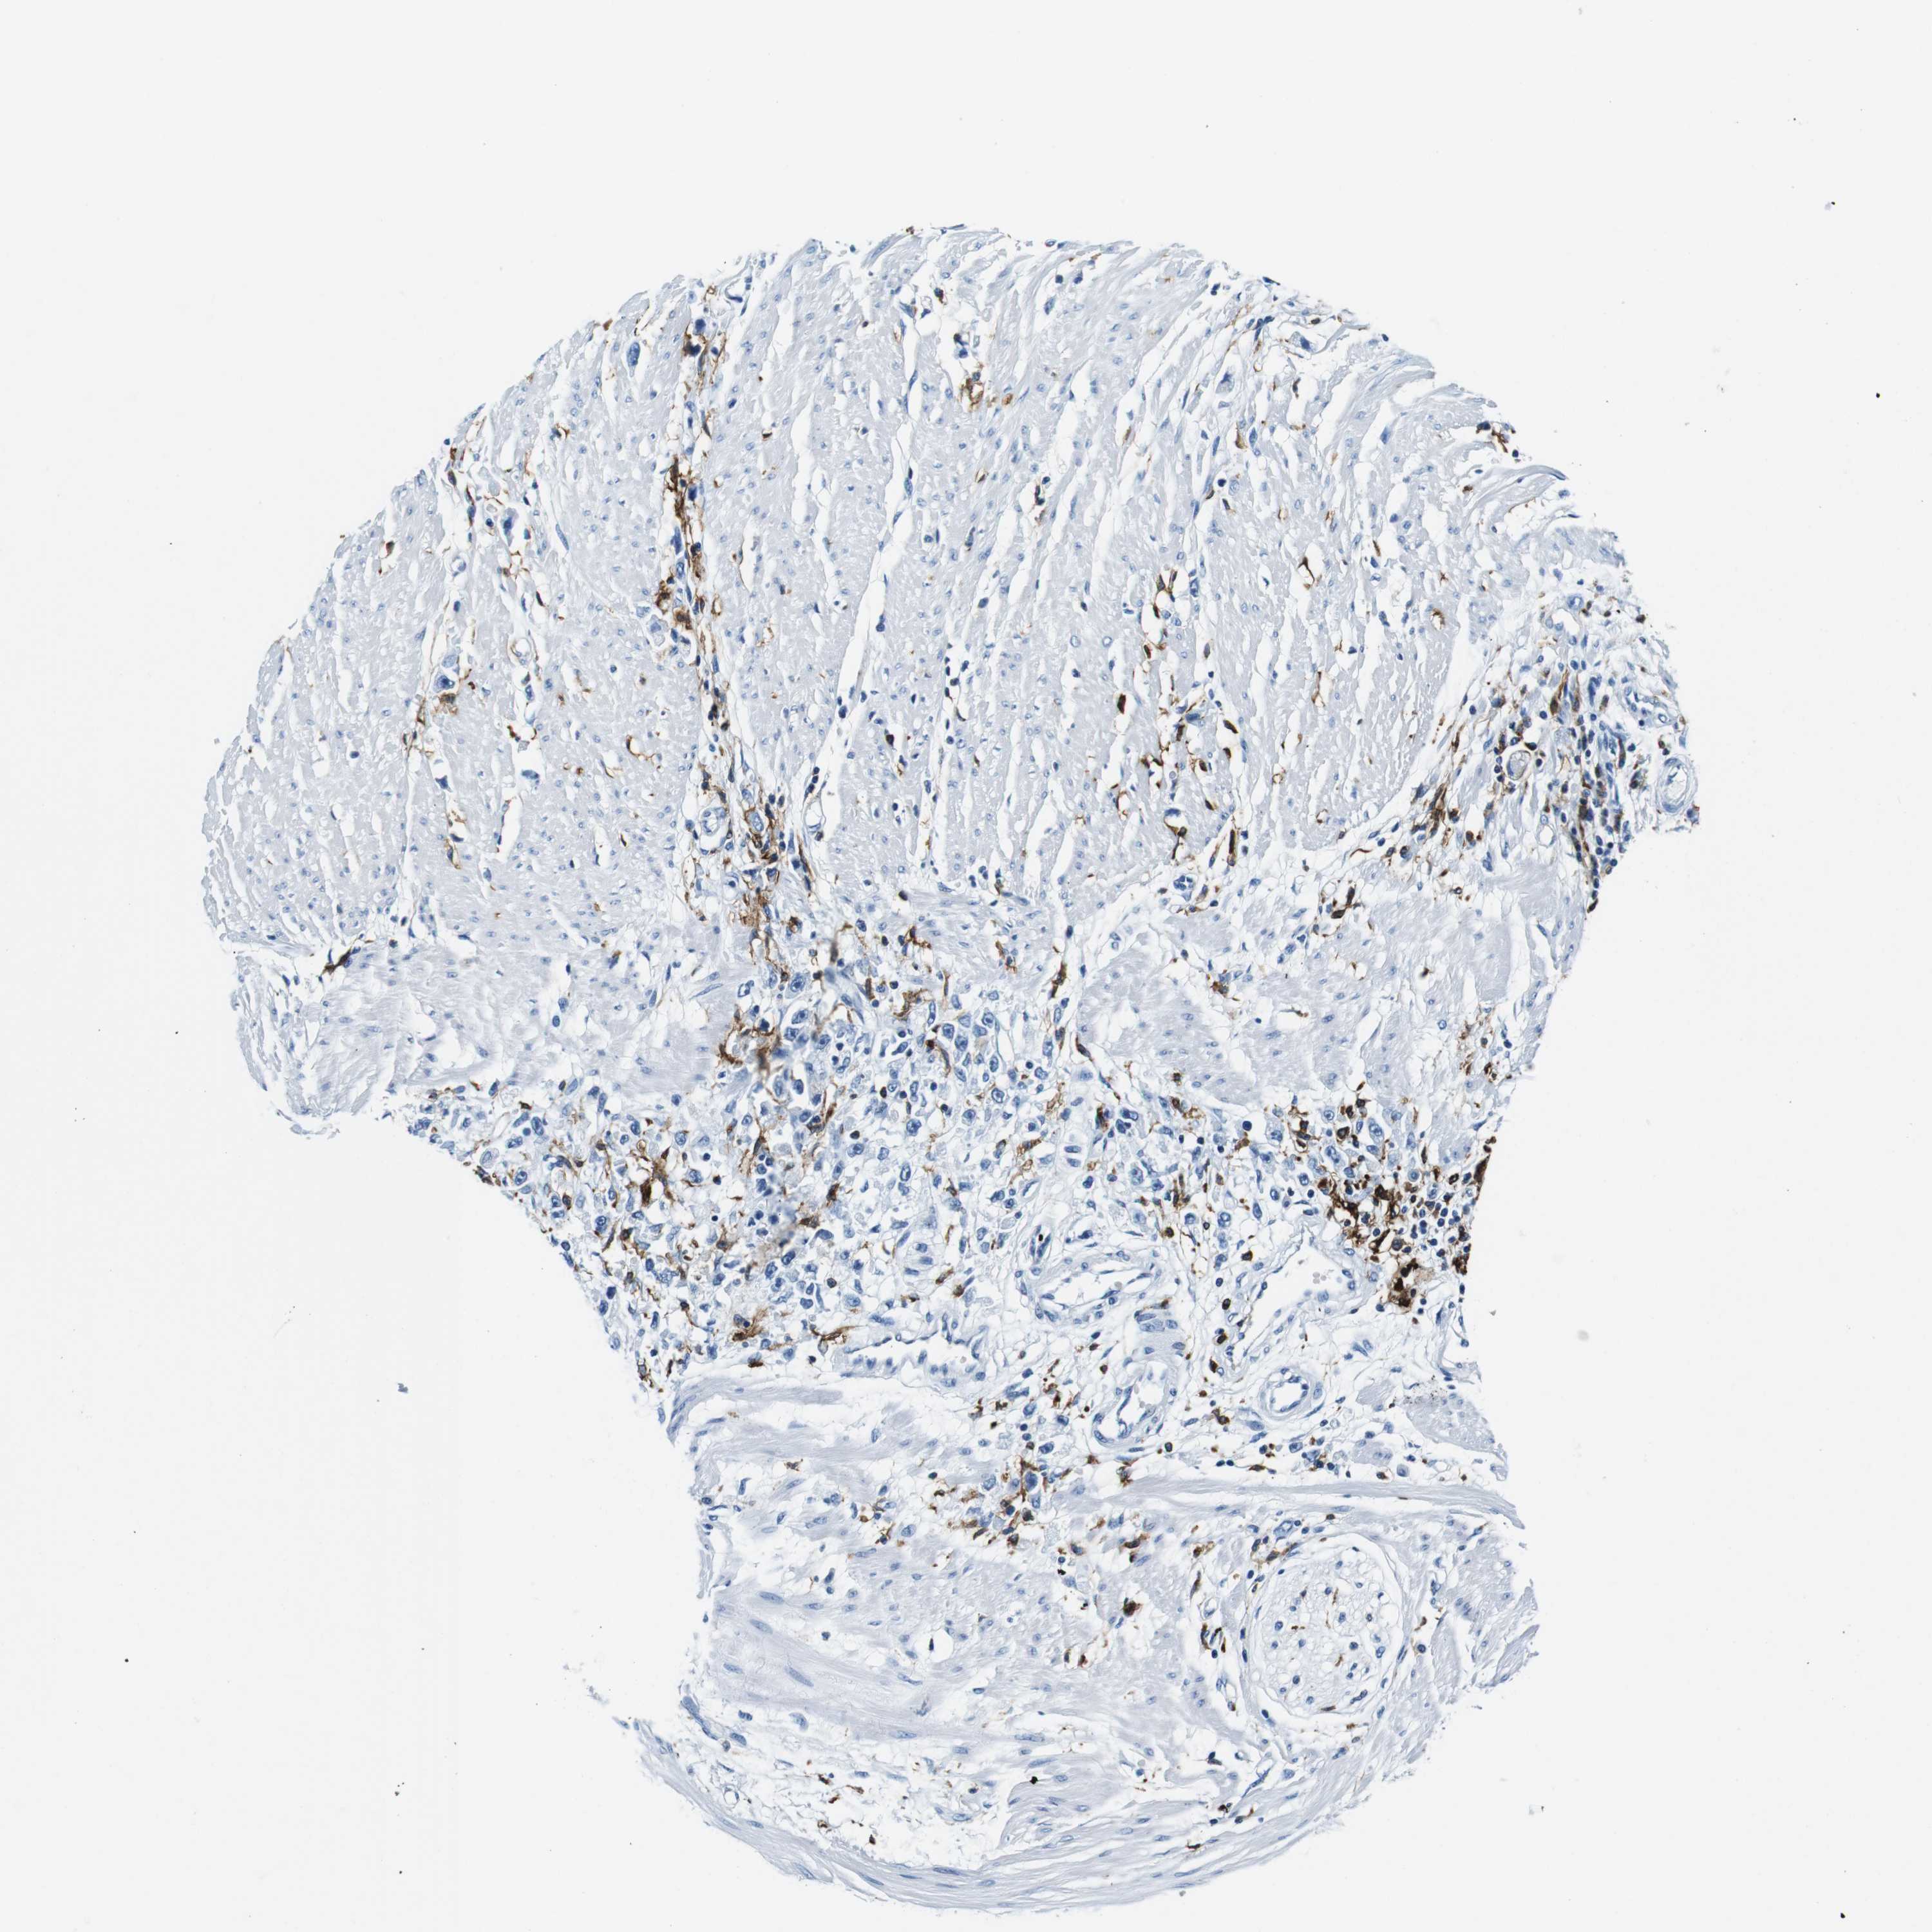

STOMACH CANCER - Protein expressioni

A mouse-over function shows sample information and annotation data. Click on an image to view it in a full screen mode. Samples can be filtered based on level of antibody staining by selecting one or several of the following categories: high, medium, low and not detected. The assay and annotation is described here.

Note that samples used for immunohistochemistry by the Human Protein Atlas do not correspond to samples in the TCGA dataset.

Antibody stainingi

Antibody staining in the annotated cell types in the current human tissue is reported as not detected, low, medium, or high, based on conventional immunohistochemistry profiling in selected tissues. This score is based on the combination of the staining intensity and fraction of stained cells.

Each image is clickable and will lead to virtual microscopy that enables deeper exploration of all samples and also displays staining intensity scores, fraction scores and subcellular localization as well as patient and tissue information for each sample.

Antibody HPA043151

Antibody CAB015400

Antibody CAB034021

Staining

High

Medium

Low

Not detected

Intensity

Strong

Moderate

Weak

Negative

Quantity

>75%

75%-25%

<25%

None

Location

Nuclear

Cytoplasmic/membranous

Cytoplasmic/membranous,nuclear

Adenocarcinoma, NOS